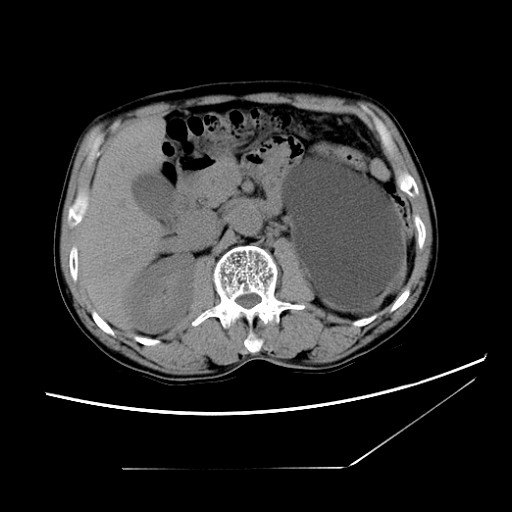

512x512 - 36KB - JPEG

腹腔镜肾切除\/部分切除术(肿瘤性、无功能肾、